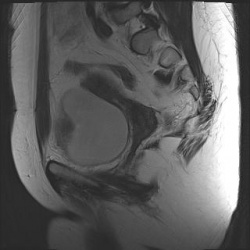

Женщина, 40 лет. Жалобы на острые боли в малом тазу.Ваше мнение? Постконтрастный: